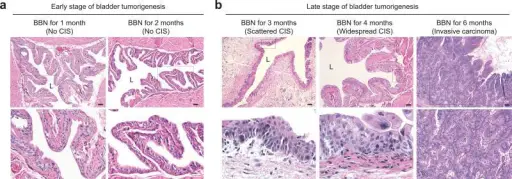

Urothelial carcinoma arises via two distinct pathways:

- Flat

- Papillary

Flat urothelial carcinoma is characterized by the invasion of a high-grade flat tumor and is associated with p53 early mutations.

Papillary urothelial carcinoma initially appears as a low-grade papillary tumor, advances to a high-grade papillary tumor, then invades, and is not linked to early p53 mutations.

Urothelial Carcinoma

Urothelial carcinoma is also known as transitional cell carcinoma.

The epithelial lining of the renal pelvis, ureter, bladder, or urethra is the source of this malignant tumor.

Urothelial carcinoma is the most typical type of bladder cancer.